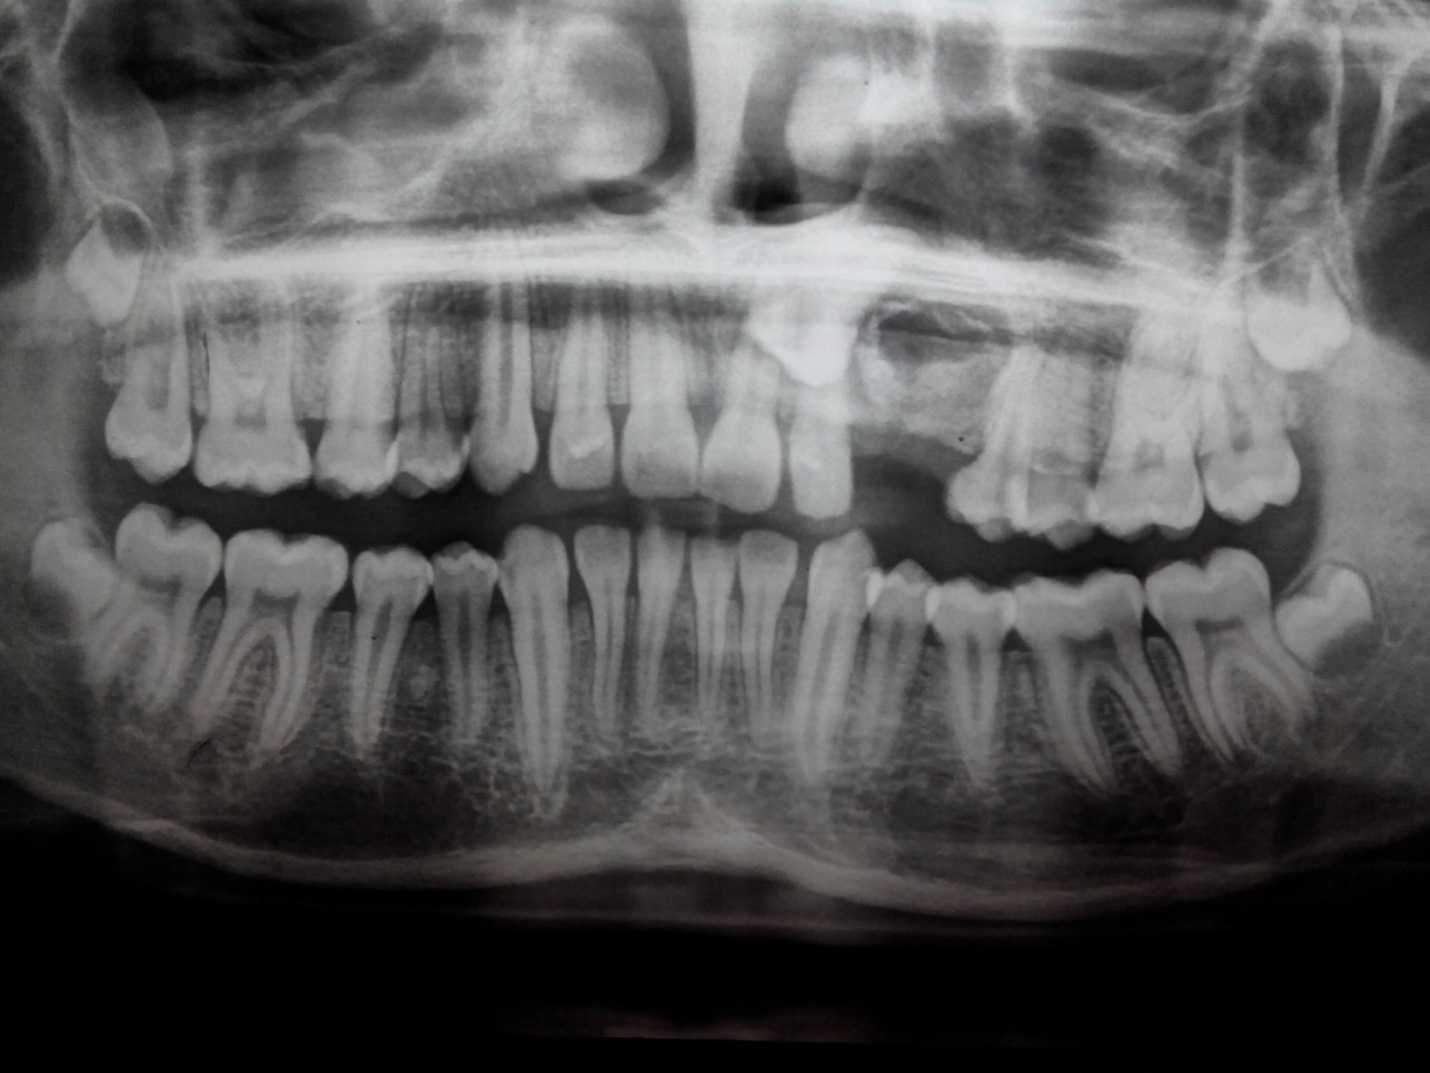

Одонтома нижней челюсти: фотографии и медицинская информация